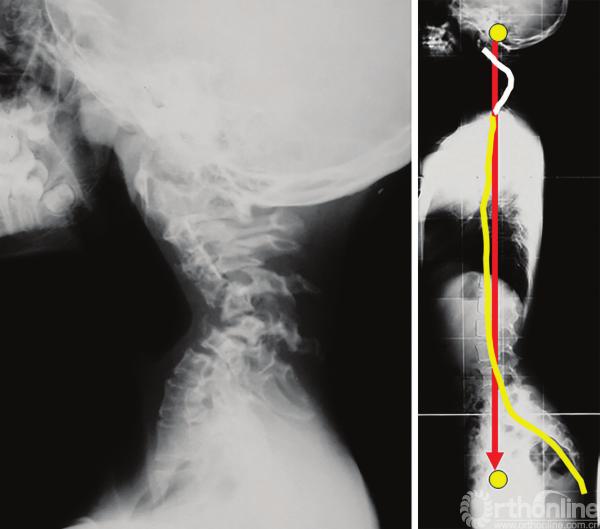

因此,我们可以通过评估外耳道(头骨的重心)和股骨头(股骨头中心,几乎是骨盆的中心)的连线来实现。Gangnet等[28]证明了这两个点(外耳道和股骨头)在正常骨盆形态和处于伸膝状态(完美平衡)的健康受试者中是垂直对齐的。

而对于通过骨盆后倾代偿平衡的患者,股骨头中点会移动到外耳道点的前下方,随后膝关节屈曲,躯干后移,最终胸椎后凸角度减小,有时还会出现上位腰椎向后滑移。PI角大的人群骨盆后倾的能力更强。

Sénégas等[15]讨论了使用踝关节过伸的方式来纠正前方失平衡的方法。尽管有时整个过程对患者来说往往是难以忍受的,但是当从外耳道引下的垂直轴自然落在股骨头前面时,我们把这称为前方失平衡。

整个脊柱的静态X线片并不代表运动过程中的真实状态。Lee等[29]研究表明,与静态侧位图像相比,术后平背患者行走时的前倾失平衡更为明显。一个可能的解释是,由于臀大肌肌肉力量减弱,在行走时不能够维持骨盆极度后倾状态。代偿现象在静态研究中起到了很大的作用,但并不能在动态研究中起到作用[30]。

有些患者存在过度后倾失平衡,表现为他们觉得“坐在自己的骨盆上”,外耳道铅垂线落在股骨头后方,行走时躯干向前倾斜。腰椎截骨术可以极大改善这些患者的状态(图3-40)。